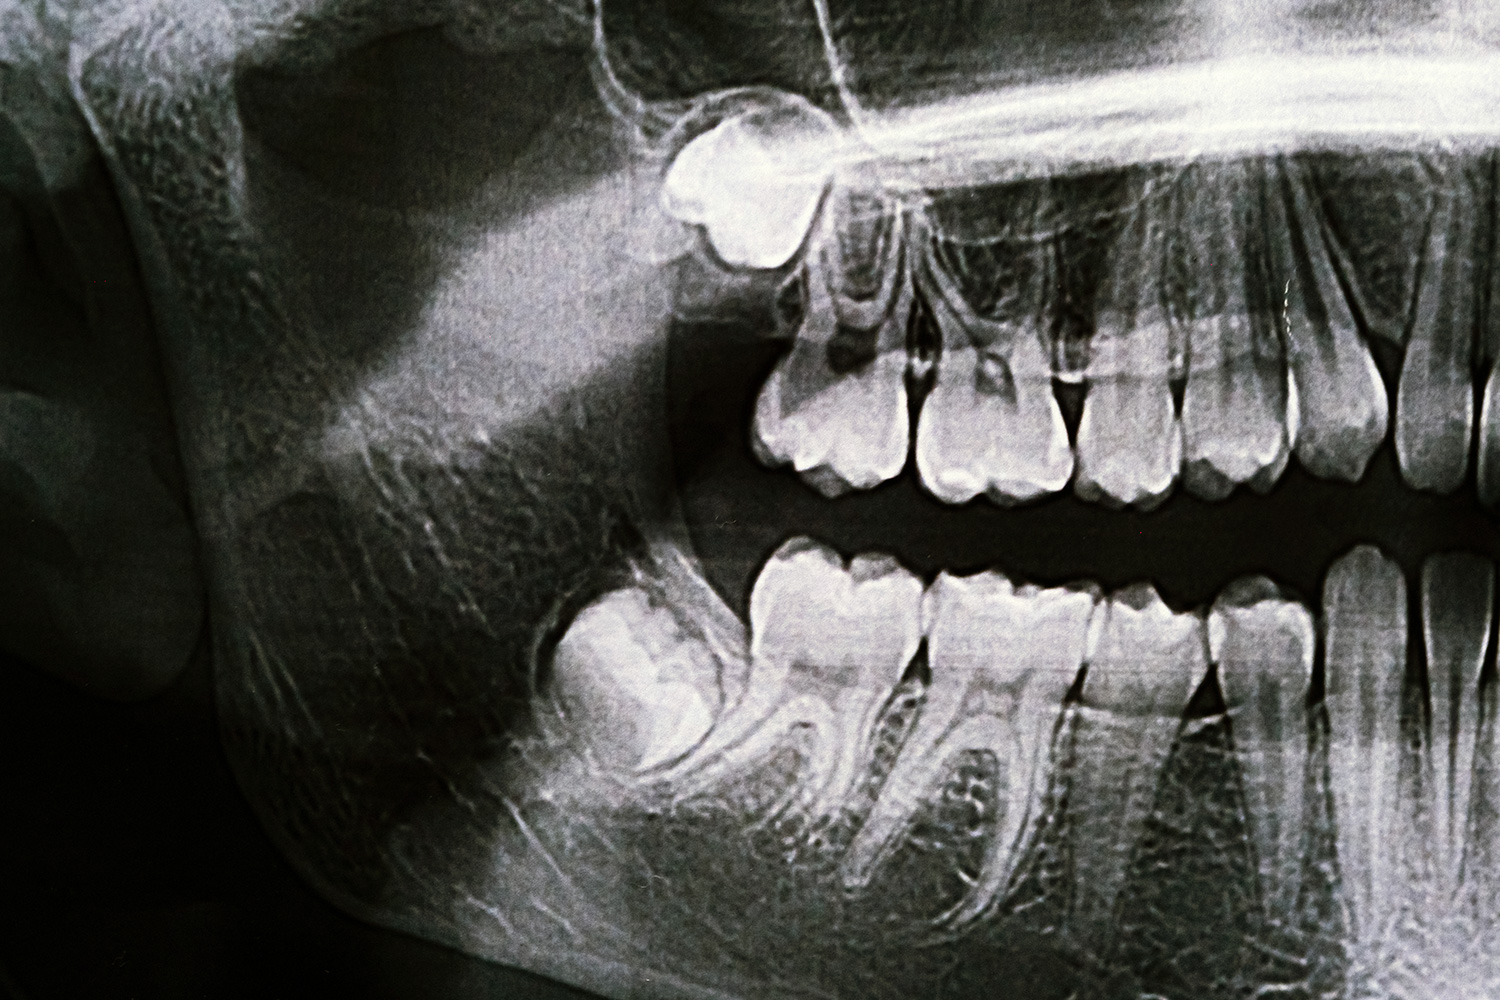

Wisdom teeth are the last molars to develop, typically appearing in late teens or early twenties. Many people lack sufficient space for wisdom teeth, causing them to become impacted. Impacted wisdom teeth can cause pain, infection, cysts, damage to adjacent teeth, and crowding.

We often recommend removing wisdom teeth before problems develop. Younger patients typically have easier recoveries because tooth roots haven’t fully formed and bone is less dense.

During wisdom teeth removal Charlotte procedures, we numb the area or provide sedation. We access the teeth through the gum tissue and bone if needed. Some teeth can be removed whole, while others need to be sectioned into smaller pieces for easier removal.